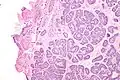

Micrograph of a Sertoli cell nodule. H&E stain.

A Sertoli cell nodule is a benign proliferation of Sertoli cells that arises in association with cryptorchidism (undescended testis).[1] They are not composed of a clonal cell population, i.e. neoplastic; thus, technically, they should not be called an adenoma.[2]

Sertoli cell nodules are unencapsulated nodules that consist of:[2][3][4]

1. cells arranged in well-formed tubules (that vaguely resemble immature Sertoli cells), with

2. bland hyperchromatic oval/round nuclei that are stratified, and

3. may contain eosinophilic (hyaline) blob in lumen (centre).